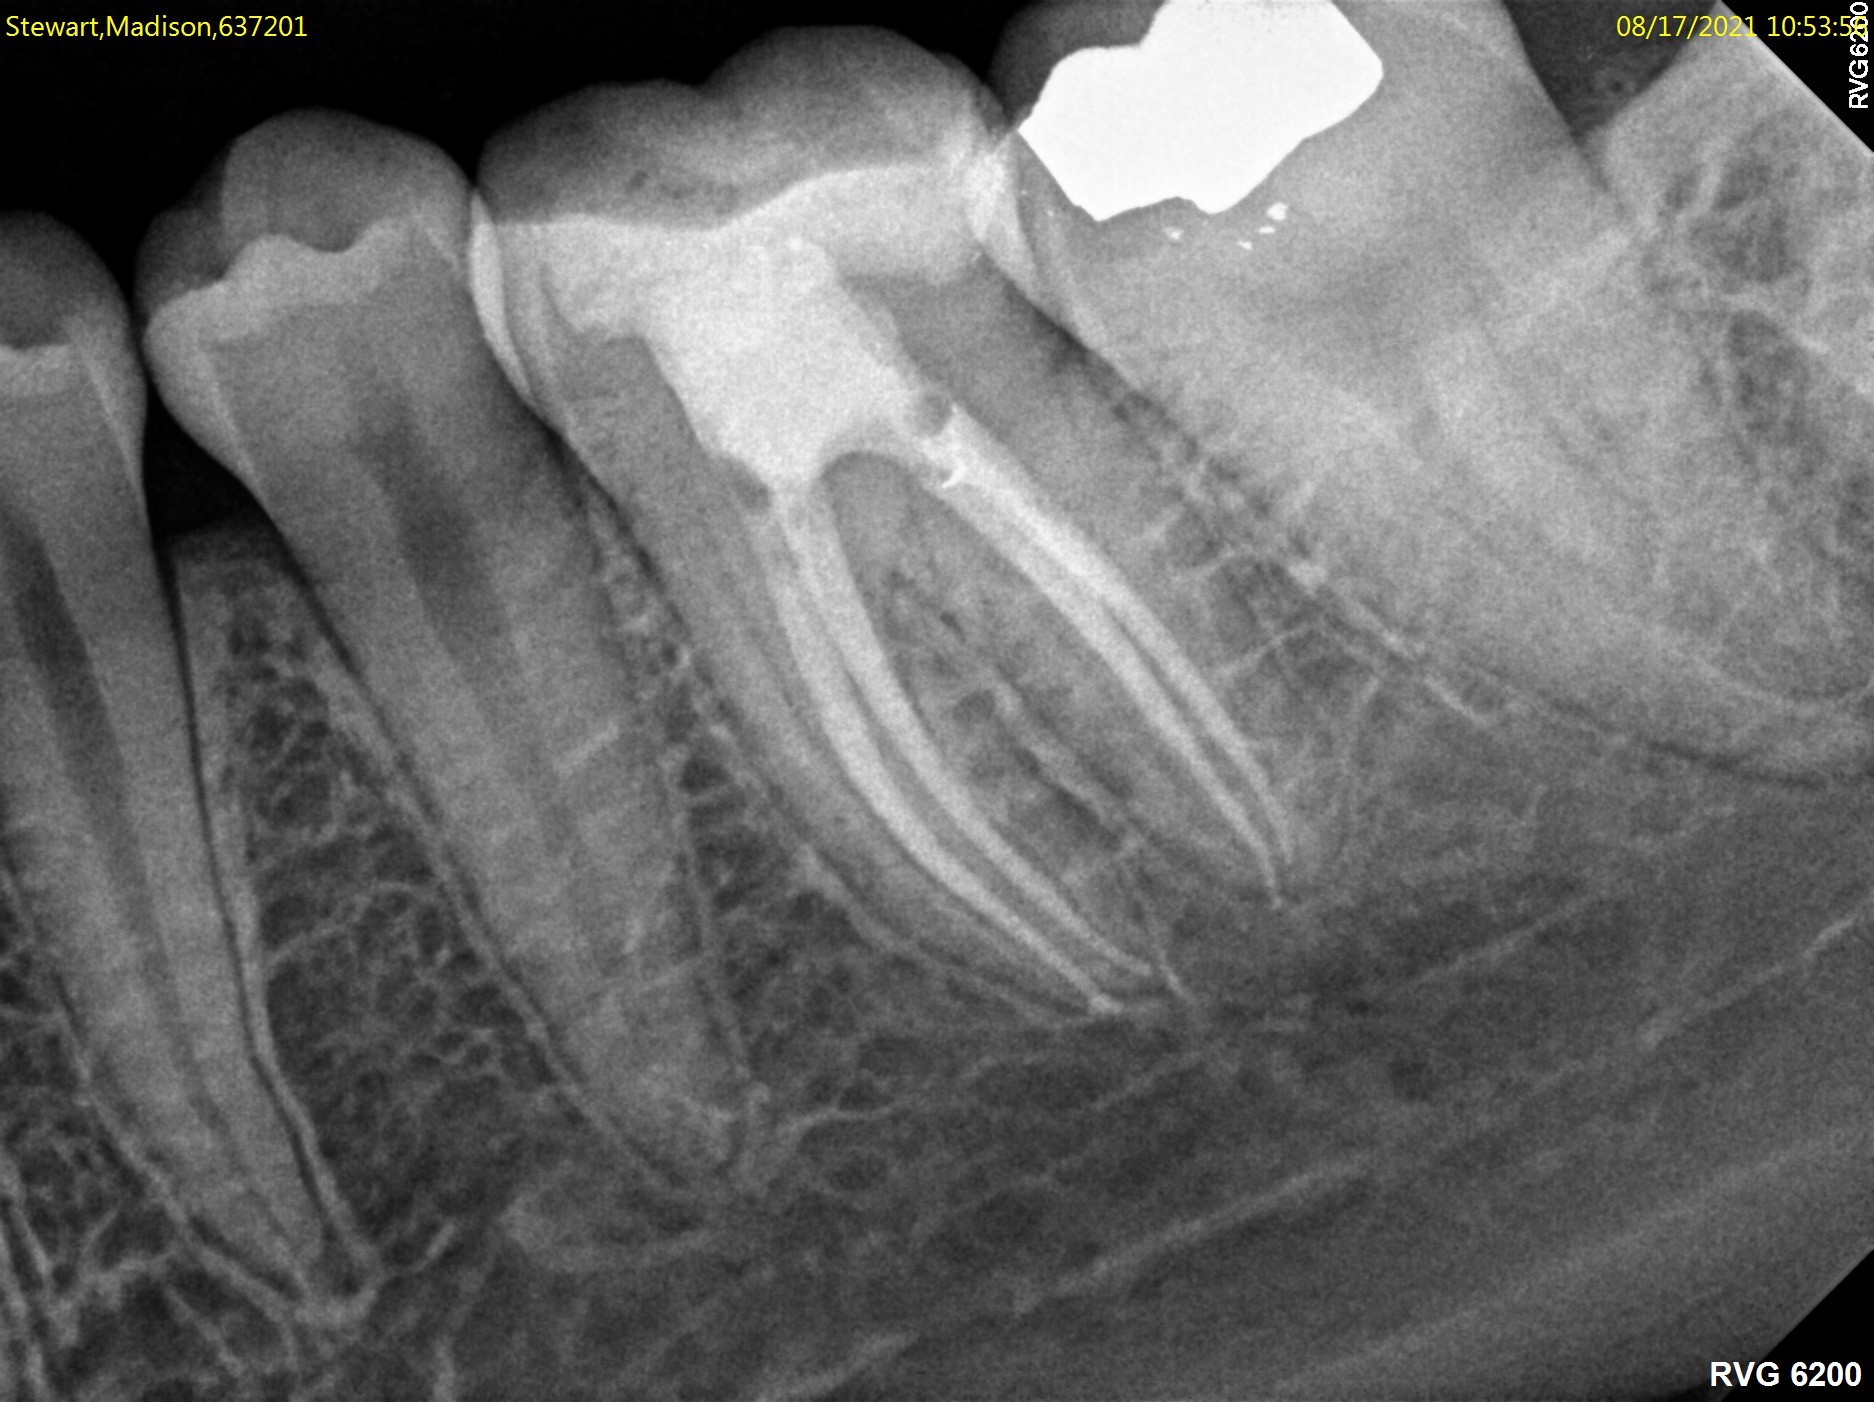

Root canal treatment is the process of going inside the pulp space and removing the inflamed or infected tissue. The space is then disinfected and sealed with special materials. Nowadays, root canal treatments are performed with advanced techniques and materials, making them far more comfortable and less time consuming. After root canal treatment is complete, your restorative dentist will usually place a crown on your tooth to safeguard against fracture.